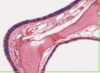

Describe valves?

- Thick collagen with occasional elastic tissue

- Both surfaces with endothelial cells

- Chordae tendinae = Fibrous